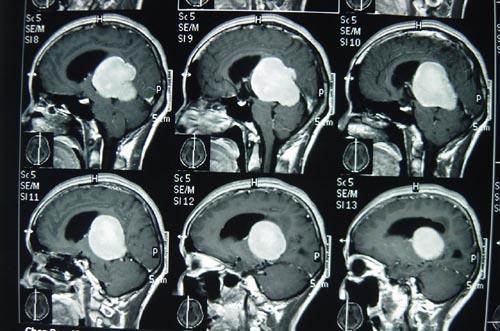

脑膜瘤如何治疗不易复发?2016年美国脑肿瘤注册中心(Central Brain Tumor Registry of the United States,CBTRUS)统计,脑膜瘤约占颅内肿瘤的36.6%。根据国际卫生组织(World Health Organization,WHO)2016版中枢神经系统肿瘤分类的定义,按照分子病理学、有无脑实质的侵犯等特点,可将脑膜瘤分为WHO Ⅰ级、WHO Ⅱ级(不典型)、WHOⅢ级(间变型)。

既往研究表明,WHOⅠ级的脑膜瘤占80%~90%,为良性肿瘤,其生长缓慢,术后不易复发,预后好于WHO Ⅱ级及Ⅲ级。新版WHO中枢神经系统肿瘤分类将侵犯周围脑组织的脑膜瘤定义为WHO Ⅱ级(不典型),故其占比有增高趋势,约为10%~15%;作为预后较差的WH O Ⅲ 级脑膜瘤(约占1%~3%),5年复发率高达90%,10年总生存率几乎为零。

脑膜瘤如何治疗不易复发?脑膜瘤目前主要依靠手术治疗,但部分脑膜瘤患者为偶然发现,并无症状;而不同部位,是位于颅底的脑膜瘤因周围解剖结构复杂,病灶与神经关系密切,使手术操作变得困难;另外,还有部分脑膜瘤患者年龄较大,手术获益与风险需要权衡。对于以上情况的脑膜瘤,如果术前能够判定肿瘤为良性,多可考虑保守的治疗策略。因此,术前影像学评估脑膜瘤的分级有着重要的临床价值。